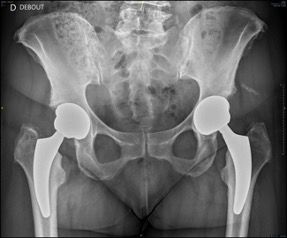

2. Restoring anatomy

Restoring the patient’s preoperative anatomy is a fundamental goal of total hip arthroplasty, applying equally to limb length, femoral offset and rotation centre of the hip. Of course, there are certain cases (dysplasia, congenital dislocation) in which we must sometimes accept a compromise, and we will return to this. The anatomy of each patient is individual [1, 2]. The neck-shaft angle, femoral offset, length and femoral version are amongst the proximal femur parameters that differ from one patient to another, and we must look to restore them as faithfully as possible. The best reproduction possible of these parameters results in a restoration of tension to the abductor muscles and lateral rotators, ensuring improved post-operative recovery [3] while reducing the risk of post-operative complications, especially instability.

Femoral offset

The anatomical positioning of short stems along the medial cortex will also allow for restoration of femoral offset. Most of the time this is an advantage over straight stems even in “standard” hips, as it is in some specific cases.

Femoral length

Restoring the closest femoral parameters to native anatomy makes it easier to reproduce femoral length. The superiority of short stems over standard straight stems in terms of restoring limb length (as with offset) has been demonstrated by Snijders et al. using a computer simulation [4].